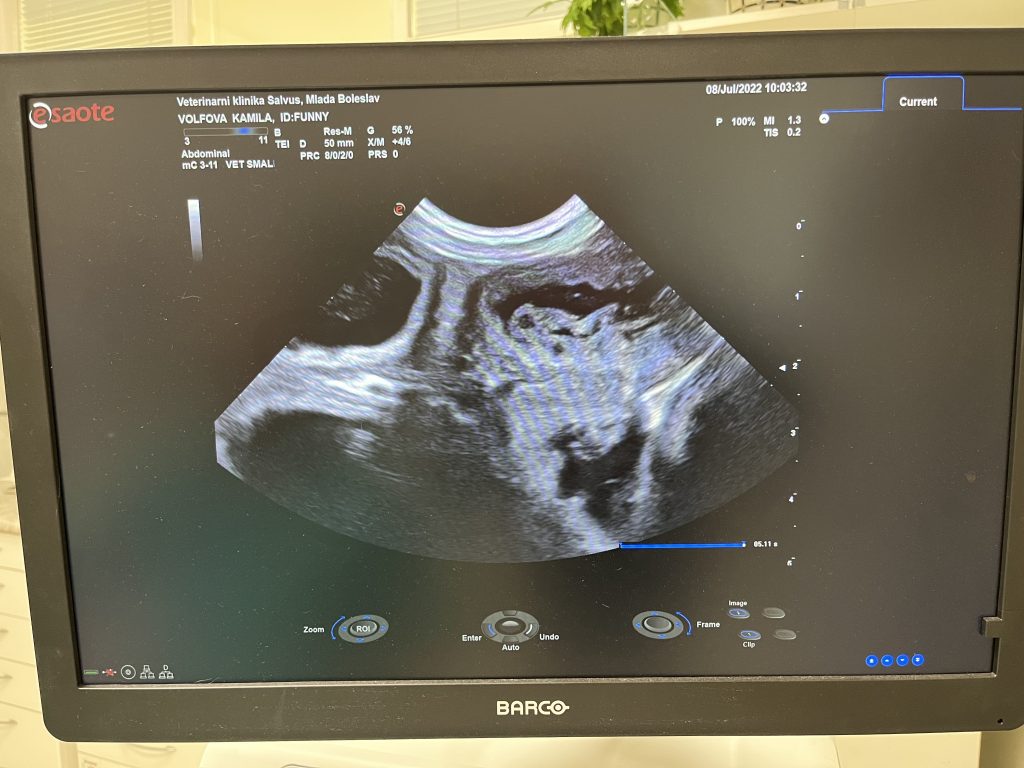

Máme potvrzeno ultrazvukem, že začátkem měsíce srpna se Fanny a Baltikovi narodí štěňátka.

Pan doktor napočítal minimálně 4 bublinky 🙂